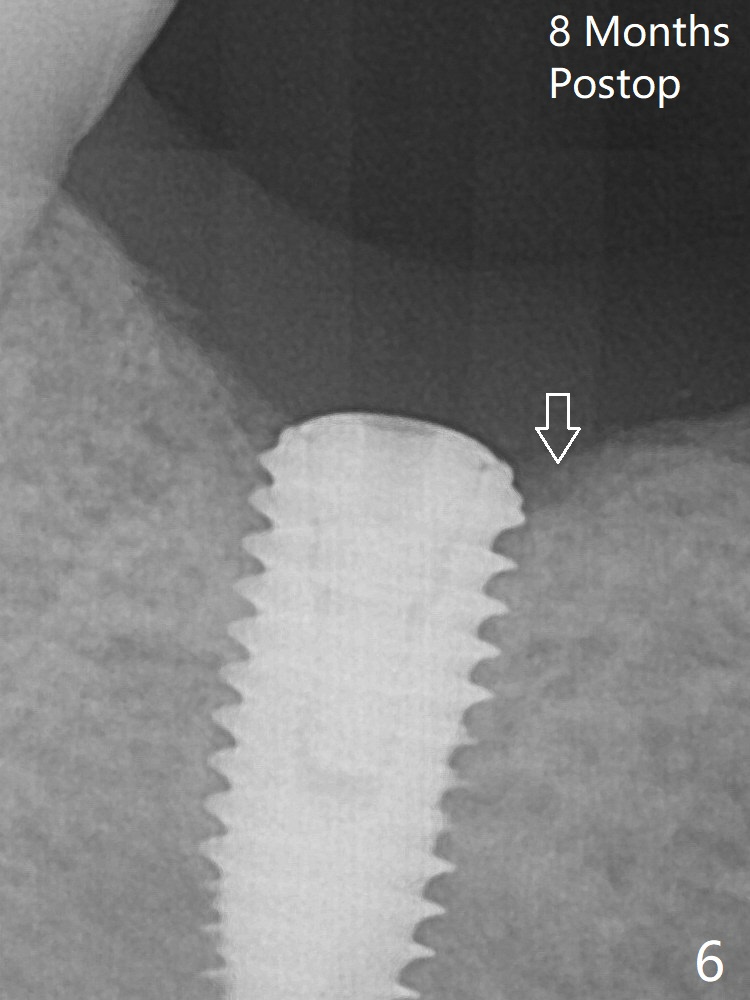

Since the Inferior Alveolar Canal is invisible (Fig.1,2 (pan should have been taken)), a 5x11.5 mm implant is placed with <20 Ncm. When a 6.5x5.5(3) mm abutment is placed, the underlying implant is turned (Fig.3).The patient returns for uncover 8 months postop; although the implant has osteointegrated apparently, the crestal bone resorbs to the implant plateau level (Fig.6 arrow). It seems that the immediate implant should be routinely placed 2-3 mm deeper.